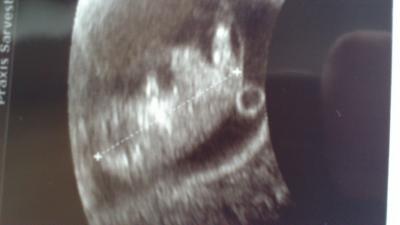

War ja eben beim Arzt und es war so unglaublich schön! Das kleine war so extrem aktiv, dass wir lange warten mussten bis die fä mal eine Aufnahme machen konnte hihi! Alles in bester Ordnung! Wir freuen uns sehr und das kleine ist schon so Groß...hier das Bildchen, bin ganz verliebt!

Bild zu der Hammer! - Forum für Mai - Mamis

Von Kopf bis zum Fuß ca. 5,5cm!

Ja ich wollte halt wissen wie groß das kleine halt insgesamt ist! Von Kopf bis zum Po sind es 3 ,5cm ;-)